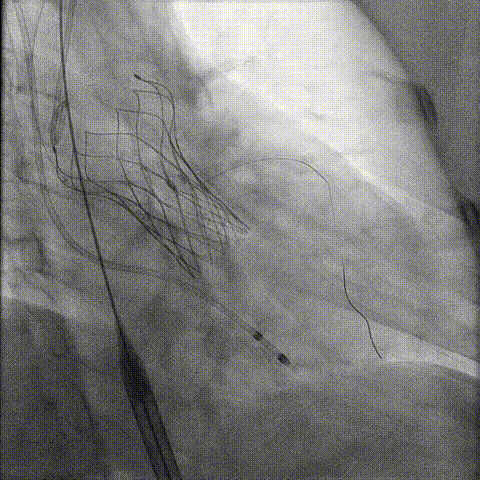

冠脉造影

手术策略和器械选择

预置Telescope™导引延长导管及导丝保护左冠,

18mm球囊预扩张再次评估冠脉闭塞风险。

介入经过及结果

Telescope™+Runthrough

18mm*40mm 预扩张

预埋 Resolute Integrity 3.5*26mm

再次评估左冠开口

第一次释放

再次评估左冠开口,考虑调整瓣膜深度

回收后调整深度,再次释放

评估左冠开口

左冠开口切线位造影

决定左冠烟囱支架保护冠脉

调整支架位置

释放冠脉支架

释放瓣膜

造影评估

支架内后扩张

根部造影